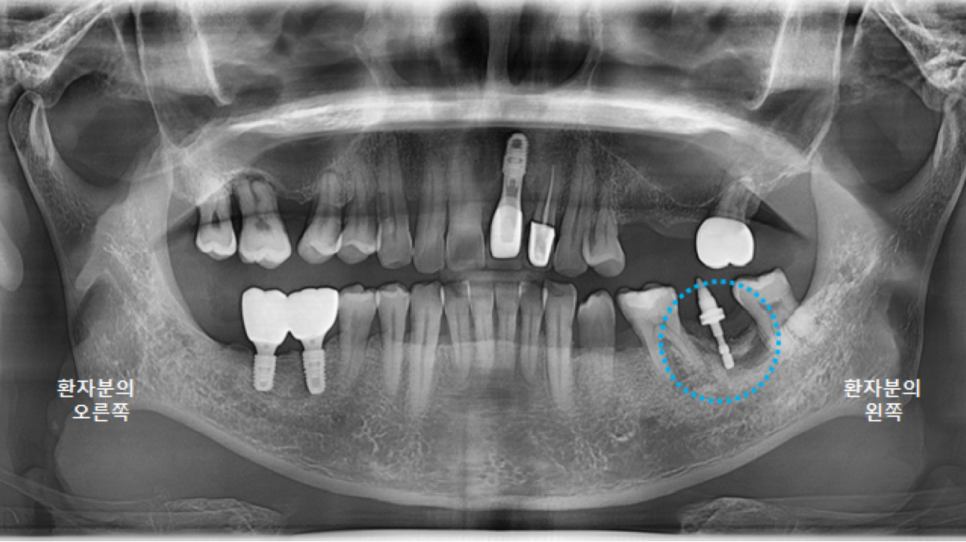

다행히 임플란트랑 뼈랑 잘 고정이되어 최종 보철물 인상채득을 시행했습니다.

본뜨는 나사를 연결해서 인상을 채득하면,

이렇게 기공소에서 맞춤 어버트먼트로 제작이됩니다.

그런데,

왼쪽 아래 큰어금니에 식립한 임플란트 앞부분에

사실 작은어금니 하나가 없는 상태입니다.

그래서 큰어금니가 앞으로 쓰러지면서

작은어금니와 큰어금니 사이에 공간이 크게 있었는데요,

환자분과 의논한 결과,

브릿지로 진행하기로 결정했습니다.